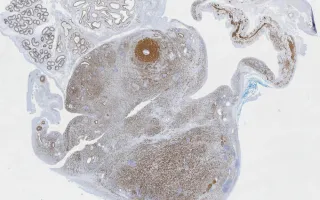

Sections demonstrate a malignant, large spindle cell neoplasm centred on the spermatic cord with fascicular

architecture and moderate-to-marked pleomorphism (anaplasia) and occasionally multiple nucleoli. These features signify the anaplastic variant in this case, which is associated with a worse prognosis. Scattered elongated rhabdomyoblasts with cytoplasmic cross-striations and globoid rhabdomyoblasts are identified. In many cells the cytoplasm appears vacuolated. Mitotic figures are easily identified (13/10 HPF), including atypical figures. Necrosis is focally present.

This slide shows desmin stain. See Related Content for H&E, SMA and myogenin stains.